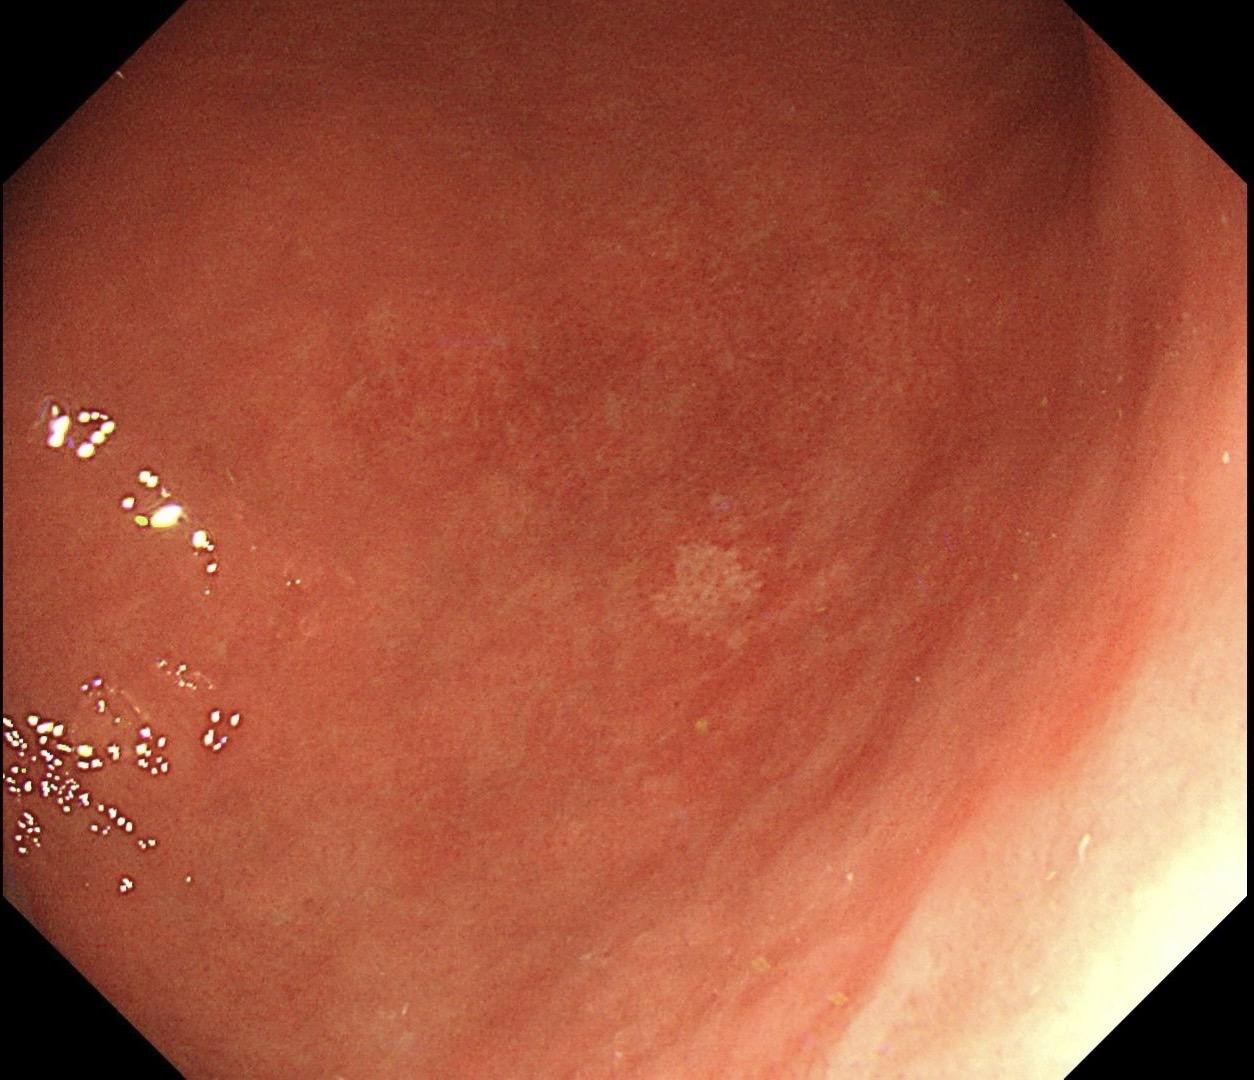

男,40岁,胃双发褪色调病变。慢性胃炎复查,3年前胃镜未见异常,Hp阳性背景,萎缩不明显,胃体下部大弯见一褪色调病变,浅凹陷,5mm左右,换用放大内镜观察,表面结构缺失,血管异型明显,未分化可能性大……胃窦后壁见一白斑,无高度差,NBI浅茶色,放大草草看了下,似有边界,IP增宽,活检待病理……小哥哥胖得几乎没脖子,腹式呼吸太明显~😖